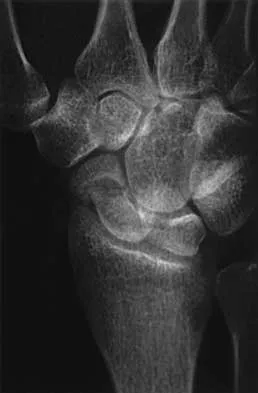

The condition shown in Figures 9a and 9b is most likely the result of

Explanation

The clinical photograph and radiograph show gout, which is the result of urate deposition in the joint and soft tissues. Radiographs frequently reveal periarticular erosions. The crystals are intracellular and negatively birefringent under the polarized microscope. Treatment for acute flares include colchicines, indomethacin, and corticosteroids (including injections). Medications such as allopurinol help prevent recurrent flares. Tophi such as that seen in this patient are often confused with and associated with infection. Wortmann RL, Kelley WM: Crystal-induced inflammation: Gout and hyperuricemia, in Harris ED, Budd RC, Firestein GS, et al (eds): Kelley's Textbook of Rheumatology, ed 7. New York, NY, Elsevier Science, 2005, pp 1402-1429. Trumble TE (ed): Hand Surgery Update 3: Hand, Elbow, & Shoulder. Rosemont, IL, American Society for Surgery of the Hand, 2003, pp 433-457.